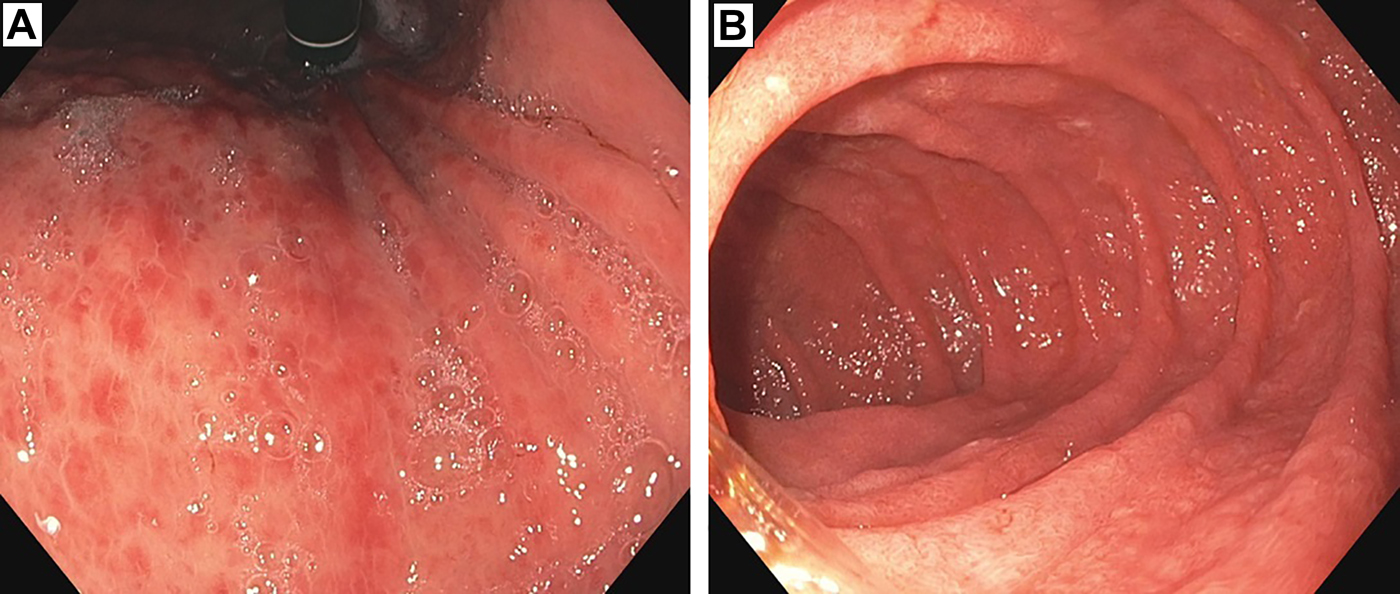

The patient underwent GI tract esophagogastroduodenoscopy 24 hours after admission. Results revealed severely inflamed, diffusely erythematous mucosa in the stomach (Figure 1A) and diffusely erythematous, congested mucosa with overlying exudate in the duodenum (Figure 1B). Gastric biopsy specimens demonstrated focally active gastritis without granuloma formation (Figure 2). Giemsa stain results were negative for Helicobacter pylori. Duodenal biopsy specimens showed active duodenitis with acute cryptitis, crypt abscess formation, and mild villous blunting without granulomas or viral inclusions (Figure 3). Results of colonoscopy with examination of the terminal ileum revealed mild colonic inflammation, extending from the rectum to the mid-ascending colon (Figure 4A). The most severe condition appeared to be in a rectosigmoid distribution. The proximal ascending colon and cecum appeared to be spared. The ileal mucosa appeared erythematous and edematous, with overlying exudate (Figure 4B). Biopsy specimens of the rectum, the sigmoid, and descending, transverse, and proximal ascending colon demonstrated mild active colitis with acute cryptitis, crypt abscesses, and neutrophils within the lamina propria (Figure 5). Biopsy specimens of the distal ileum showed moderate active ileitis with acute cryptitis, crypt abscesses, and focal architectural distortion (Figure 6).

An image taken during esophagogastroduodenoscopy 2 weeks after ipilimumab administration revealed (A) severely inflamed, diffusely erythematous mucosa in the stomach and (B) diffusely erythematous, congested mucosa with overlying exudate in the duodenum.